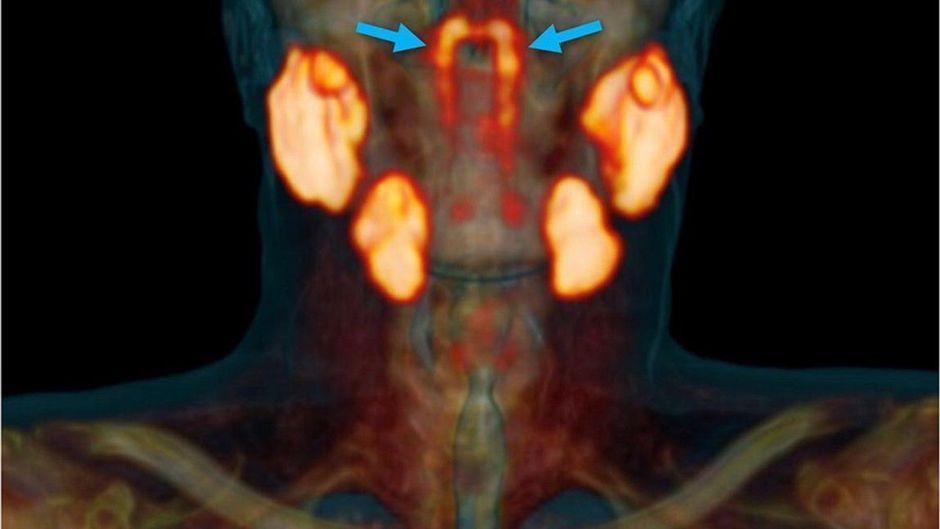

Wie niederländische Wissenschaftler durch Zufall herausfanden, befinden sich im Kopf noch unbekannte Speicheldrüsen. Ihre Ergebnisse veröffentlichten die Forscher in der Septemberausgabe des Branchenblatts "Radiotherapy and Oncology Journal".